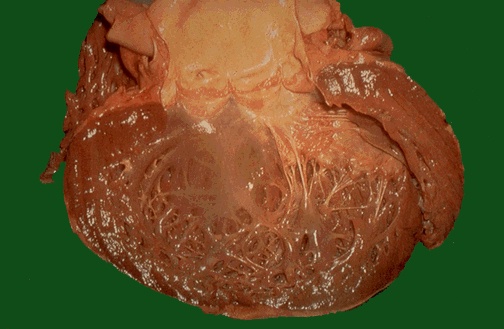

| Here is a large, dilated left ventricle that is typical of a dilated, or congestive, cardiomyopathy. Many of these cases have no known etiology (a so-called "idiopathic dilated cardiomyopathy") while others may be associated with chronic alcoholism or with inherited genetic mutations. The heart grossly is very enlarged and flabby. |